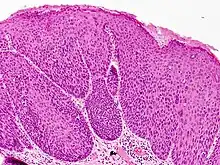

Bowenoid papulosis is a cutaneous condition characterized by the presence of pigmented verrucous papules on the body of the penis.[1]:730[2]:408 They are associated with human papillomavirus, the causative agent of genital warts.[3] The lesions have a typical dysplastic histology and are generally considered benign, although a small percentage will develop malignant characteristics.

It is considered as a pre-malignant condition. Other terms used to describe the condition are: Erythroplasia of Queyrat, Squamous cell carcinoma in situ and Bowen's disease. The term bowenoid papulosis was coined in 1977 by Kopf and Bart and is named after dermatologist John Templeton Bowen.[4][5][6] The term "intraepithelial neoplasia" defines a premalignant intraepithelial change.